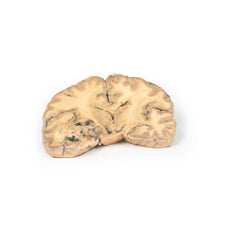

3D Printed Left Cerebral Infarct

The patient was a 51-year old woman who had a cerebro-vascular accident resulting in a left

hemiplegia 2 years prior to death. At necropsy, she had severe generalized atherosclerosis and an old left

ventricular myocardial infarct with an overlying mural thrombus.

A coronal section of the cerebral hemispheres shows irregular cystic cavities in the territory of

distribution of the right middle cerebral artery. The cavities of the infarct have irregular, yellow walls and

show partial collapse. There is compensatory dilatation of the left lateral ventricle. On the posterior aspect,

the arteries below the mammillary bodies were moderately atheromatous, although this is difficult to visualise

macroscopically.

Because of the underlying history of myocardial disease with the presence of the mural

thrombus, it is assumed that her cerebral infarct was probably caused by a thromboembolus.